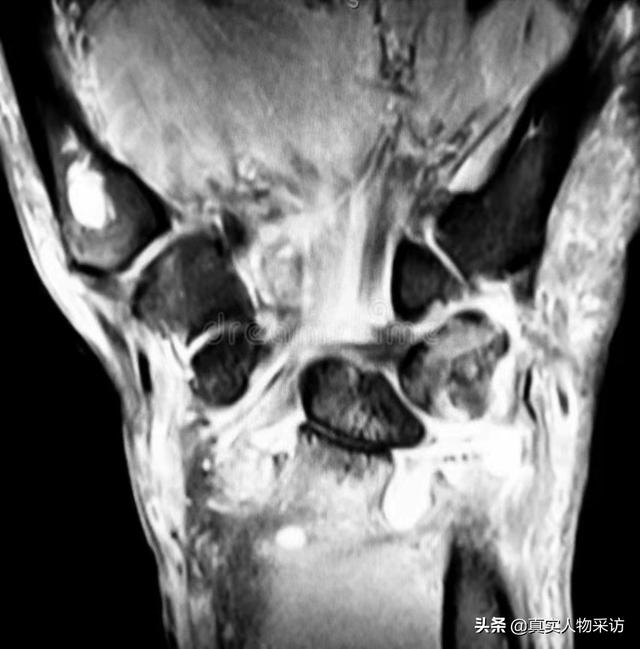

自从宗力走丢以后,我为了找儿子,早就把自己的腿跑坏了。不仅半月板磨损得厉害,还得了滑mo炎,积液多得脚都抬不起来,经常要往外抽积液。

(为了找儿子,自己的腿都快跑断了)

这对着急寻找儿子的我,无异于雪上加霜。现在我隔三差五就要去医院看腿,已经无法走远路了,不仅腿上离不开膏药,还要同时吃好多药。